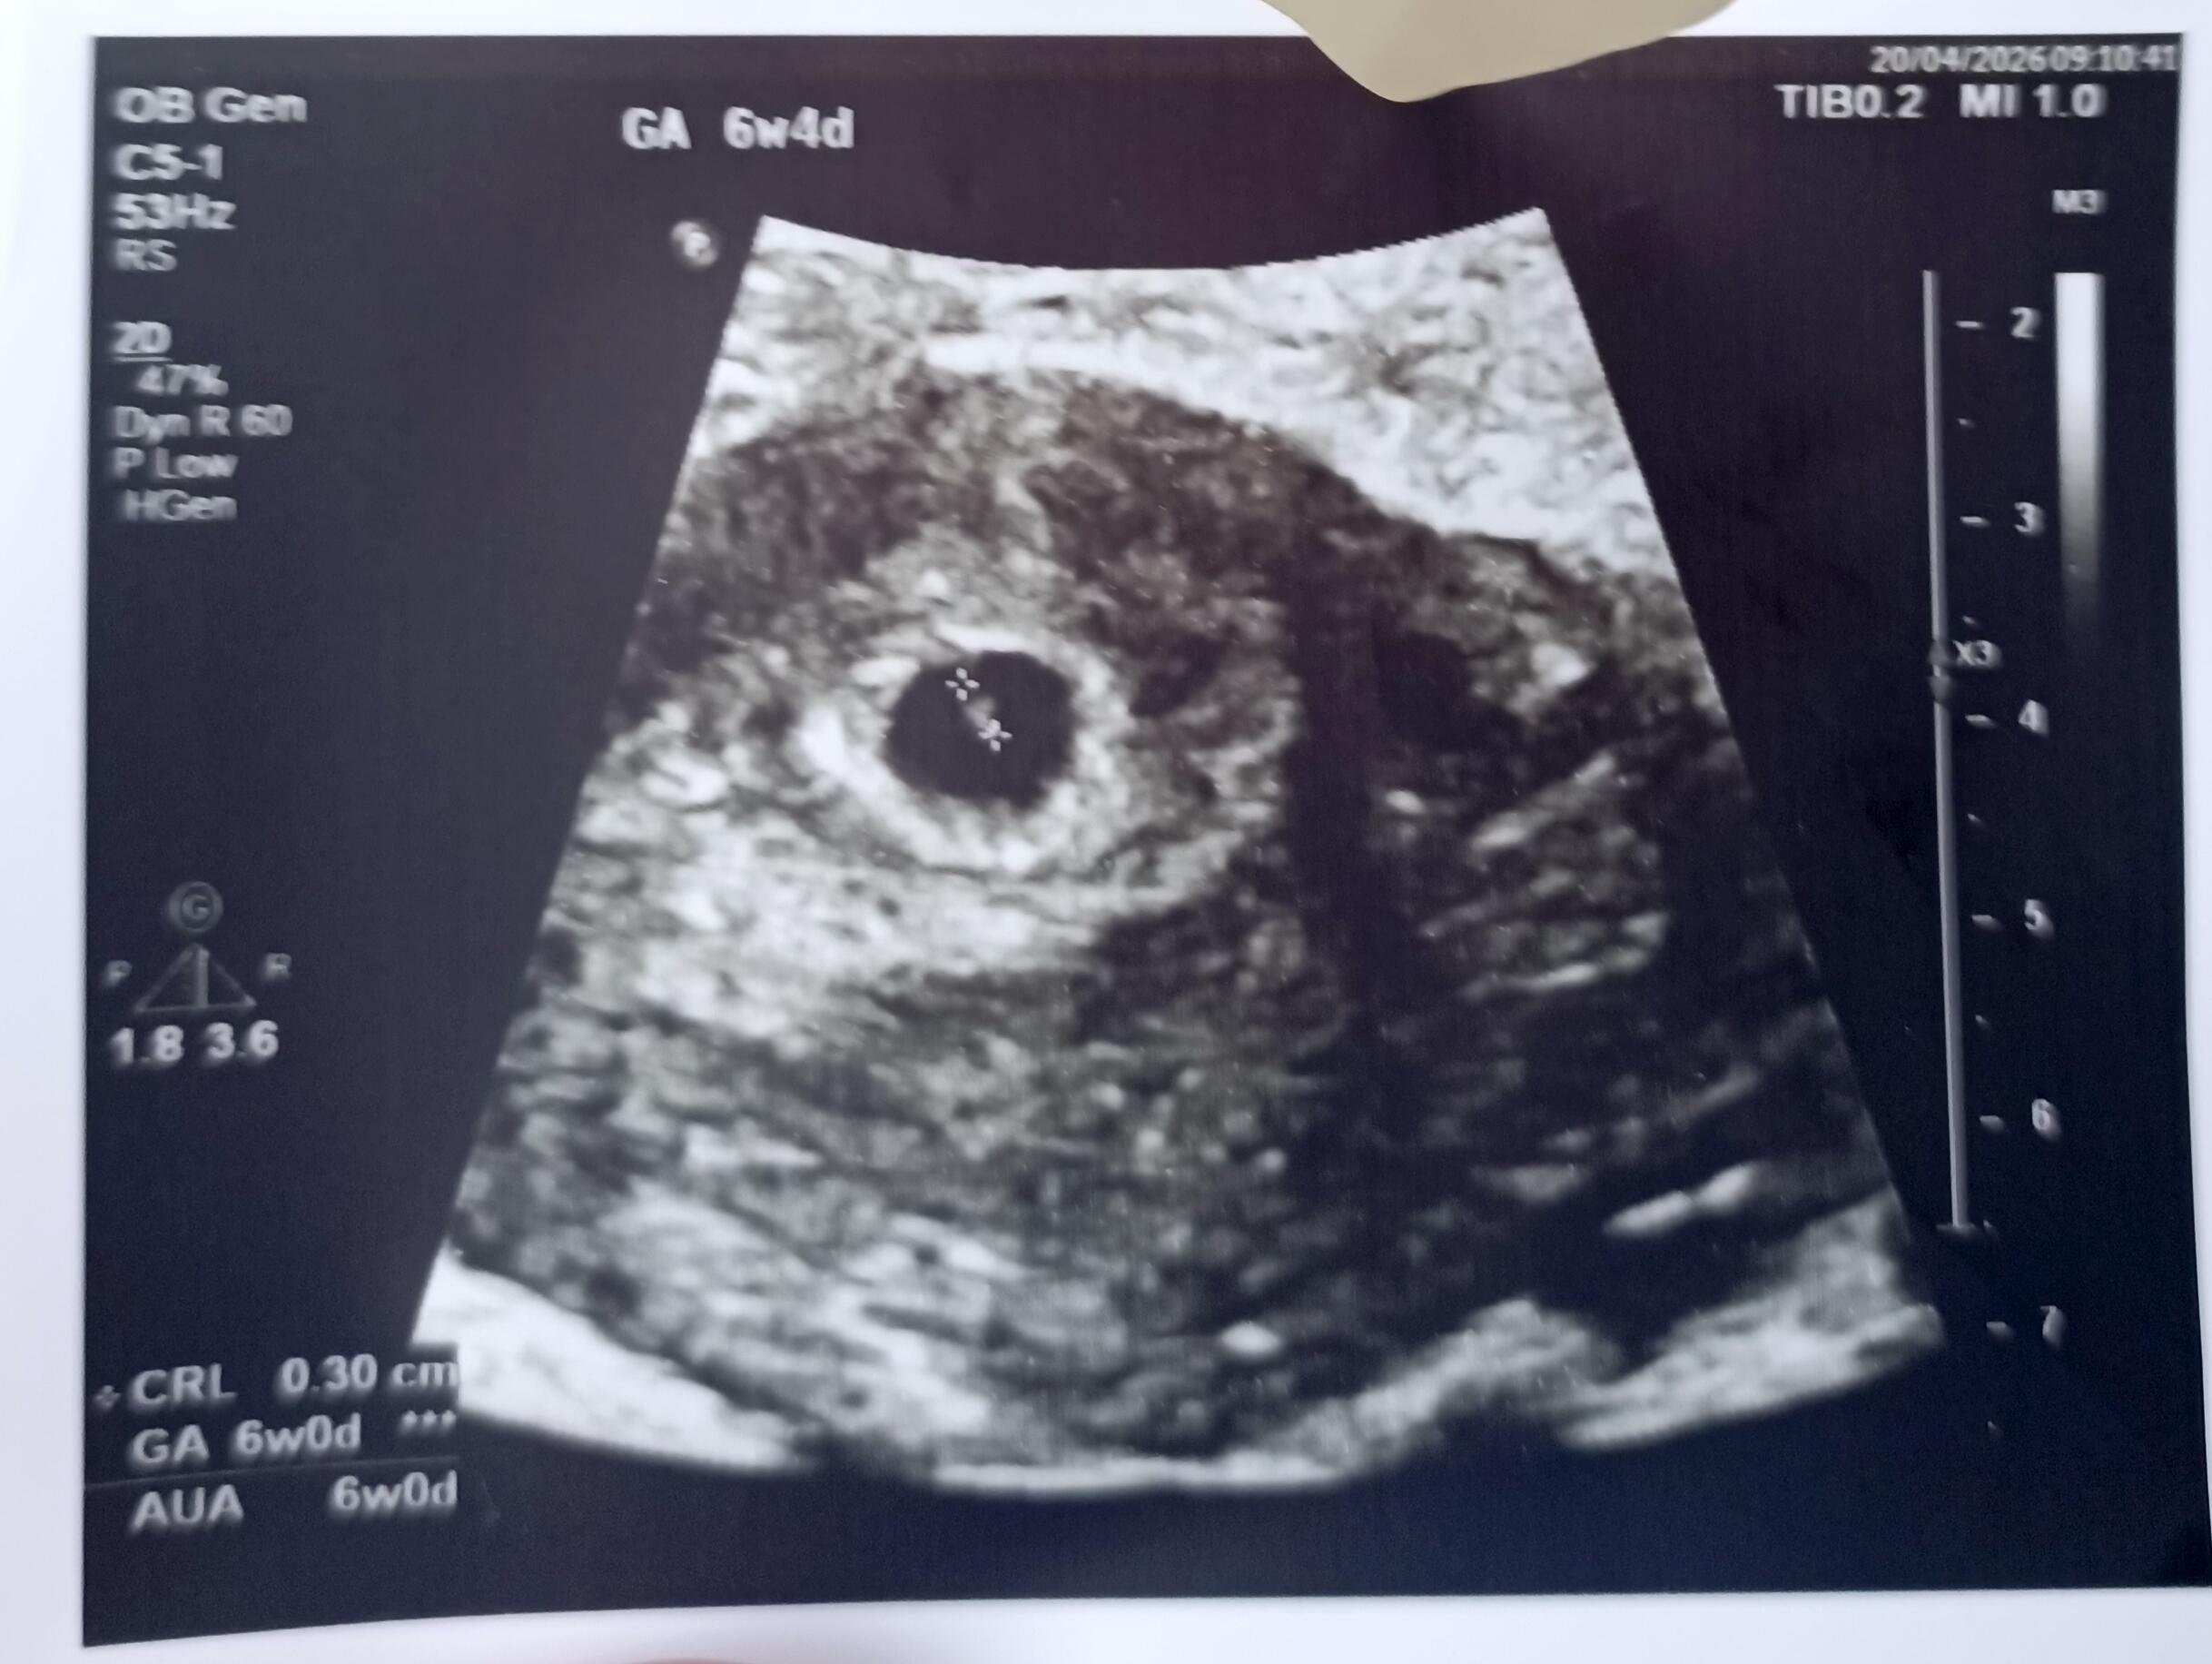

Kese şekline göre kız bebek diyecegim canim

Kızlarimda kesem öyle değildi